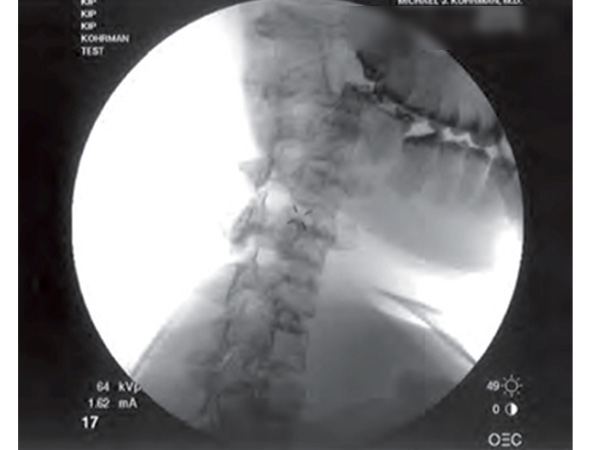

RSD注射模体帮助*个人学习和磨练技能,以适当的针放置各种介入技术。荧光针的放置可以被现实地教授或实践,而不用担心与新鲜或冷冻尸体相关的生物污染危害。

在透视下,解剖标志的外观和感觉是很重要的,可以通过使用RSD注射模体来证明。尾侧、硬膜外、选择性神经和根阻滞、内侧分支阻滞、关节突注射和交感神经阻滞都可以被证明。练习射频针放置、椎间盘针放置以及肩部、髋关节和耻骨联合注射技术——所有这些都在您自己的实验室或教学设施的方便和安全。现在没有必要处理有关与尸体相关的生物危害的地方、州和联邦法规。